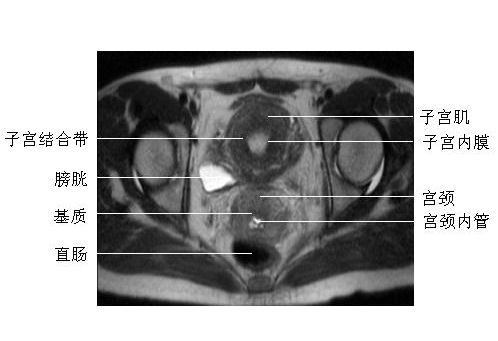

女性盆腔横断面-MRI图

女性盆腔横断面-MRI